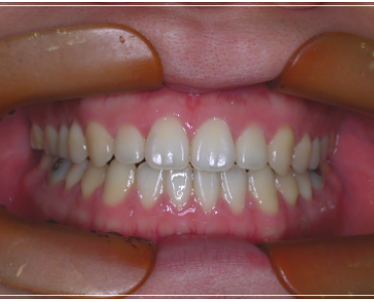

이 처럼 입을 다물어도 어금니만

맞물린 채 앞니가 맞물리지 않는 증상을

개방교합이라고 부르는데요.

개방교합은 입을 다물때 안쪽

어금니만 맞닿고 앞니 쪽은 닿지 않아

입술이 붕 떠 있는 상태를 말했어요.

성장 중의 부정적인 문제로 인해

발생한 개방교합은 보통 치아를

교정하면 위와 같은 불편함이 해결 될

것이라고 생각하시는 분들이 많은데,